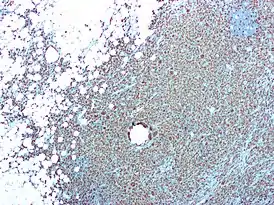

Хронический пиелонефрит с уменьшением размера почек и очаговым истончением кортикального слоя. Измерение длины почек на ультразвуковом изображении показано знаком «+» и пунктирной линией.[4]

- Content initially copied from: Hansen, Kristoffer; Nielsen, Michael; Ewertsen, Caroline (2015). “Ultrasonography of the Kidney: A Pictorial Review”. Diagnostics. 6 (1): 2. DOI:10.3390/diagnostics6010002. ISSN 2075-4418. PMC 4808817. PMID 26838799. (CC-BY 4.0)